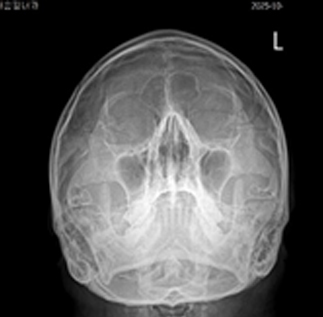

후비루 증상은 부비동 엑스레이나 비강 내시경을 통하여 비부비동염 여부를 확인해야 하며, 기침형 천식은 기관지 유발 시험, 호기 산화질소, 객담 호산구 검사 등으로 진단할 수 있습니다. 한편 위식도 역류 질환은 식도로 역류된 위속의 내용물로 인해 불편한 증상이나 합병증이 유발되는 상태를 말하며, 24시간 식도 산도 검사나 위내시경을 통하여 진단할 수 있습니다. 위산이 식도를 넘어 인두와 후두까지 역류하여 점막을 자극하는 경우 후두 내시경을 통하여 인후두 역류 질환을 진단할 수 있습니다.

상기도 기침 증후군 기침형 천식 위산 역류 질환

치료 전 기관지 유발 시험 검사 위식도 역류 질환

img img img

치료 후 기관지 유발 시험 검사 양성 인후두 역류 질환